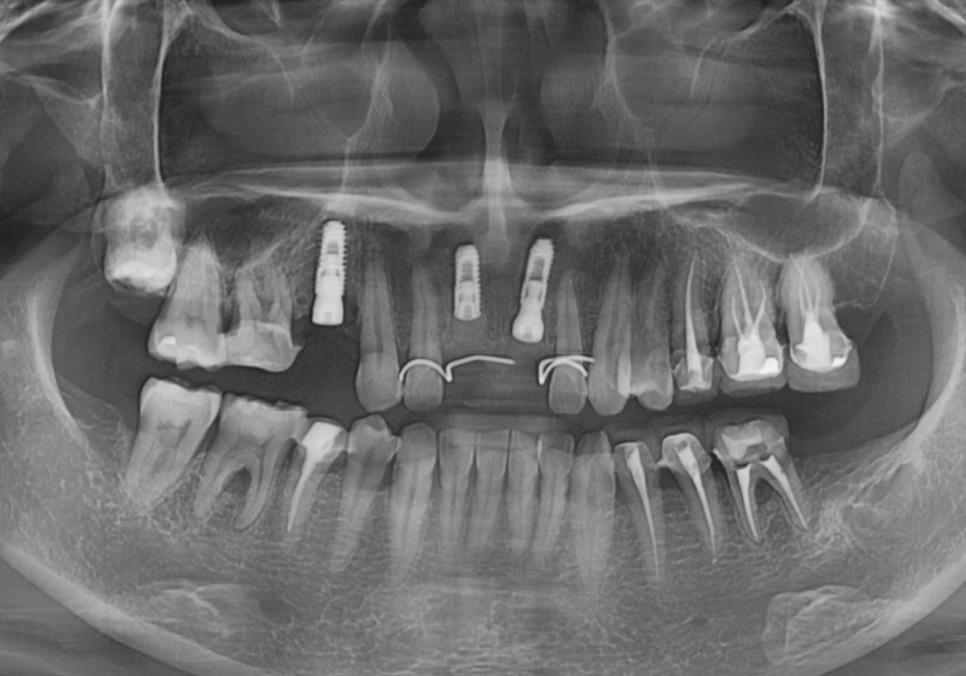

방사선 사진을 확인해 보니

예상보다 상태가 좋지 않았습니다.

신경치료 후 포스트(금속 기둥)까지

해둔 상태였고 뿌리 쪽으로

2차 충치가 상당히 진행되었습니다.

포스트까지 해두셨다는 건

크라운을 제작 당시,

치아 손상이 컸다는 것을 뜻하는데요.

250513

치아를 흔들어보니

안쪽이 많이 삭아,

약간의 흔들림까지 있었죠.

크라운을 제거하면 치아가 부러질

가능성이 높은 상태였기 때문에

재치료보다는 발치 후 임플란트가

더 안전하고 오래 쓰실 수 있는 방법이라고

환자분께 솔직하게 상태를 설명드렸습니다.